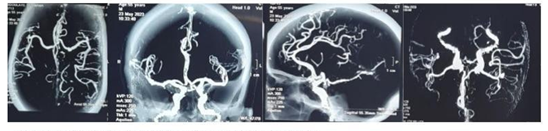

The head CT Scan performed showed a thick left parieto-temporal hyperdensity witha slight midline shift making think of spontaneous acute subdural hematoma (SASH) (Figure 1). The blood investigations (Prothrombin time and Activated partial thromboplastin time; Complete Blood Count; Ionogram; Blood sugar) were normal. Brain angio-CT didn’t show any abnormality (Figure 2). The diagnosis of spontaneous acute subdural hematoma has been retained despite the unavailability of angiography in our context. The patient benefited from conservative treatment under observation (analgesic (combined stage 1 and 2), saline-based fluid intake, osmotherapy for 48 hours, and anti-hypertensive on cardiological advice). The head CT Scan performed 02 days later was unchanged outside a slight remission of meningeal hemorrhage (Figure 3).

Figure 2 Cerebral angio-CT reveals no vascular anomalies.

The current literature, consisting mainly of surgical case reports, does not offer a consensus etiological diagnostic approach. No diagnostic algorithm for etiological research has been evaluated and validated in this situation, so clinical and paraclinical investigations may vary from one center to another. The examinations most frequently proposed are CT scan, MRI, angiography (to investigate a vascular anomaly), and conventional hemostasis work-up in search of coagulopathy.2 The angio- CT performed on this patient showed no detectable vascular anomaly or hypertensive angiopathy. The blood investigations were normal as well.